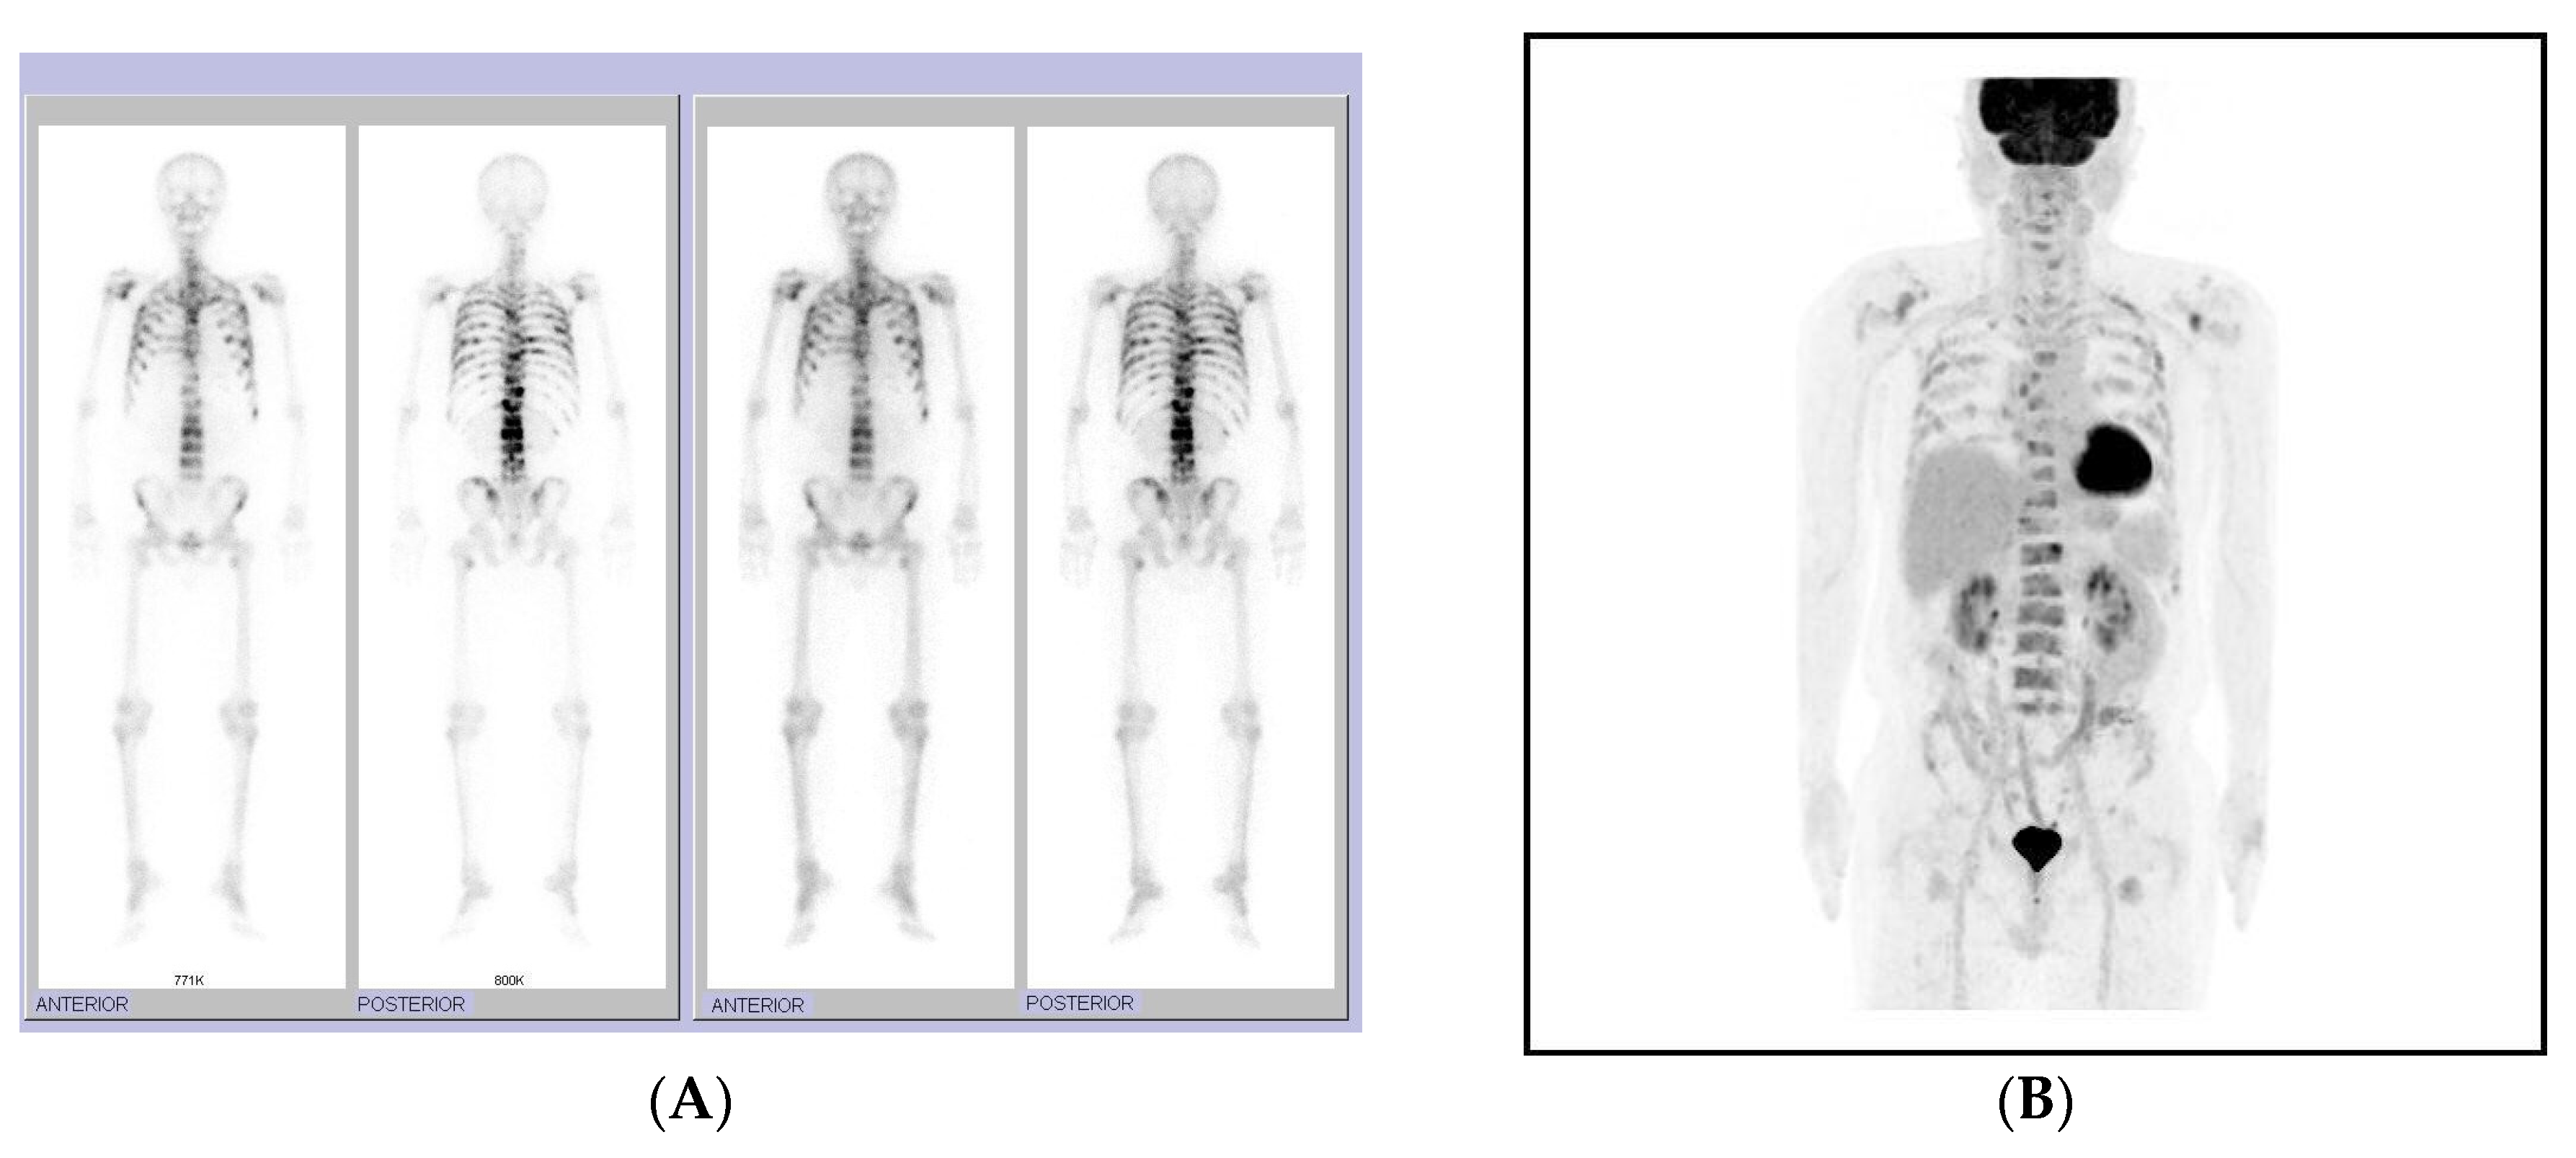

2. Detailed Case Description